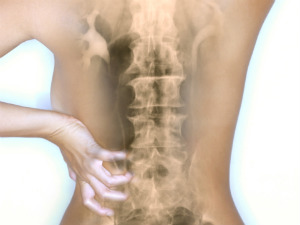

रीढ़ की हड्डी की चोट का जल्द होगा इलाज

वैज्ञानिकों का कहना है कि जल्द ही रीढ़ की हड्डी की चोट का इलाज दांत की कोशिकाओं का उपयोग कर किया जा सकेगा। जापान की नागोया युनिवर्सिटी के एक दल ने दंत मज्जा को ऐसे चूहों में प्रतिरोपण किया जिनकी कमर टूट गई थी और पाया कि इनकी टांग में कुछ हरकत हुई।

वैज्ञानिकों को उम्मीद है कि इससे रीढ़ की हड्डी की दिक्कतों वालें लोगों के जीवन में तब्दीली आएगी। डेली मिरर की एक रिपोर्ट के अनुसार दांत के मध्य में पाई जाने वाली मज्जा ने तंत्रिका कोशिका को खत्म होने से रोक दिया और कई तंत्रिकाओं को पुनरूज्जीवित कर दिया जिसने चूहों की रीढ़ की हड्डी को समर्थन देने वाली अन्य कोशिकाओं के विकास में मदद की।